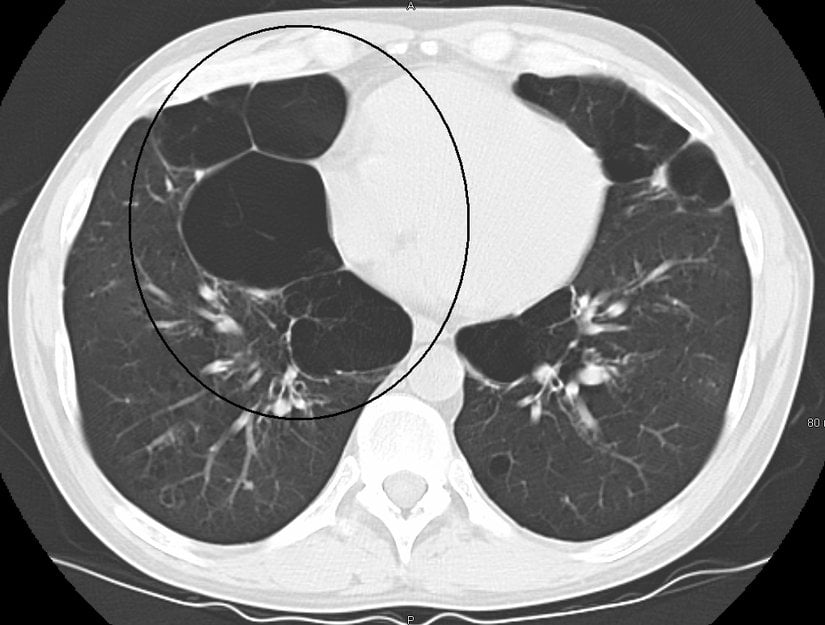

- Bilgisayarlı tomografi: Akciğerlerinizin BT taraması, amfizemin saptanmasına yardımcı olabilir ve KOAH ameliyatından fayda sağlayıp sağlayamayacağınızı belirlemenize yardımcı olabilir. Akciğer kanseri taraması için BT taramaları da kullanılabilir.